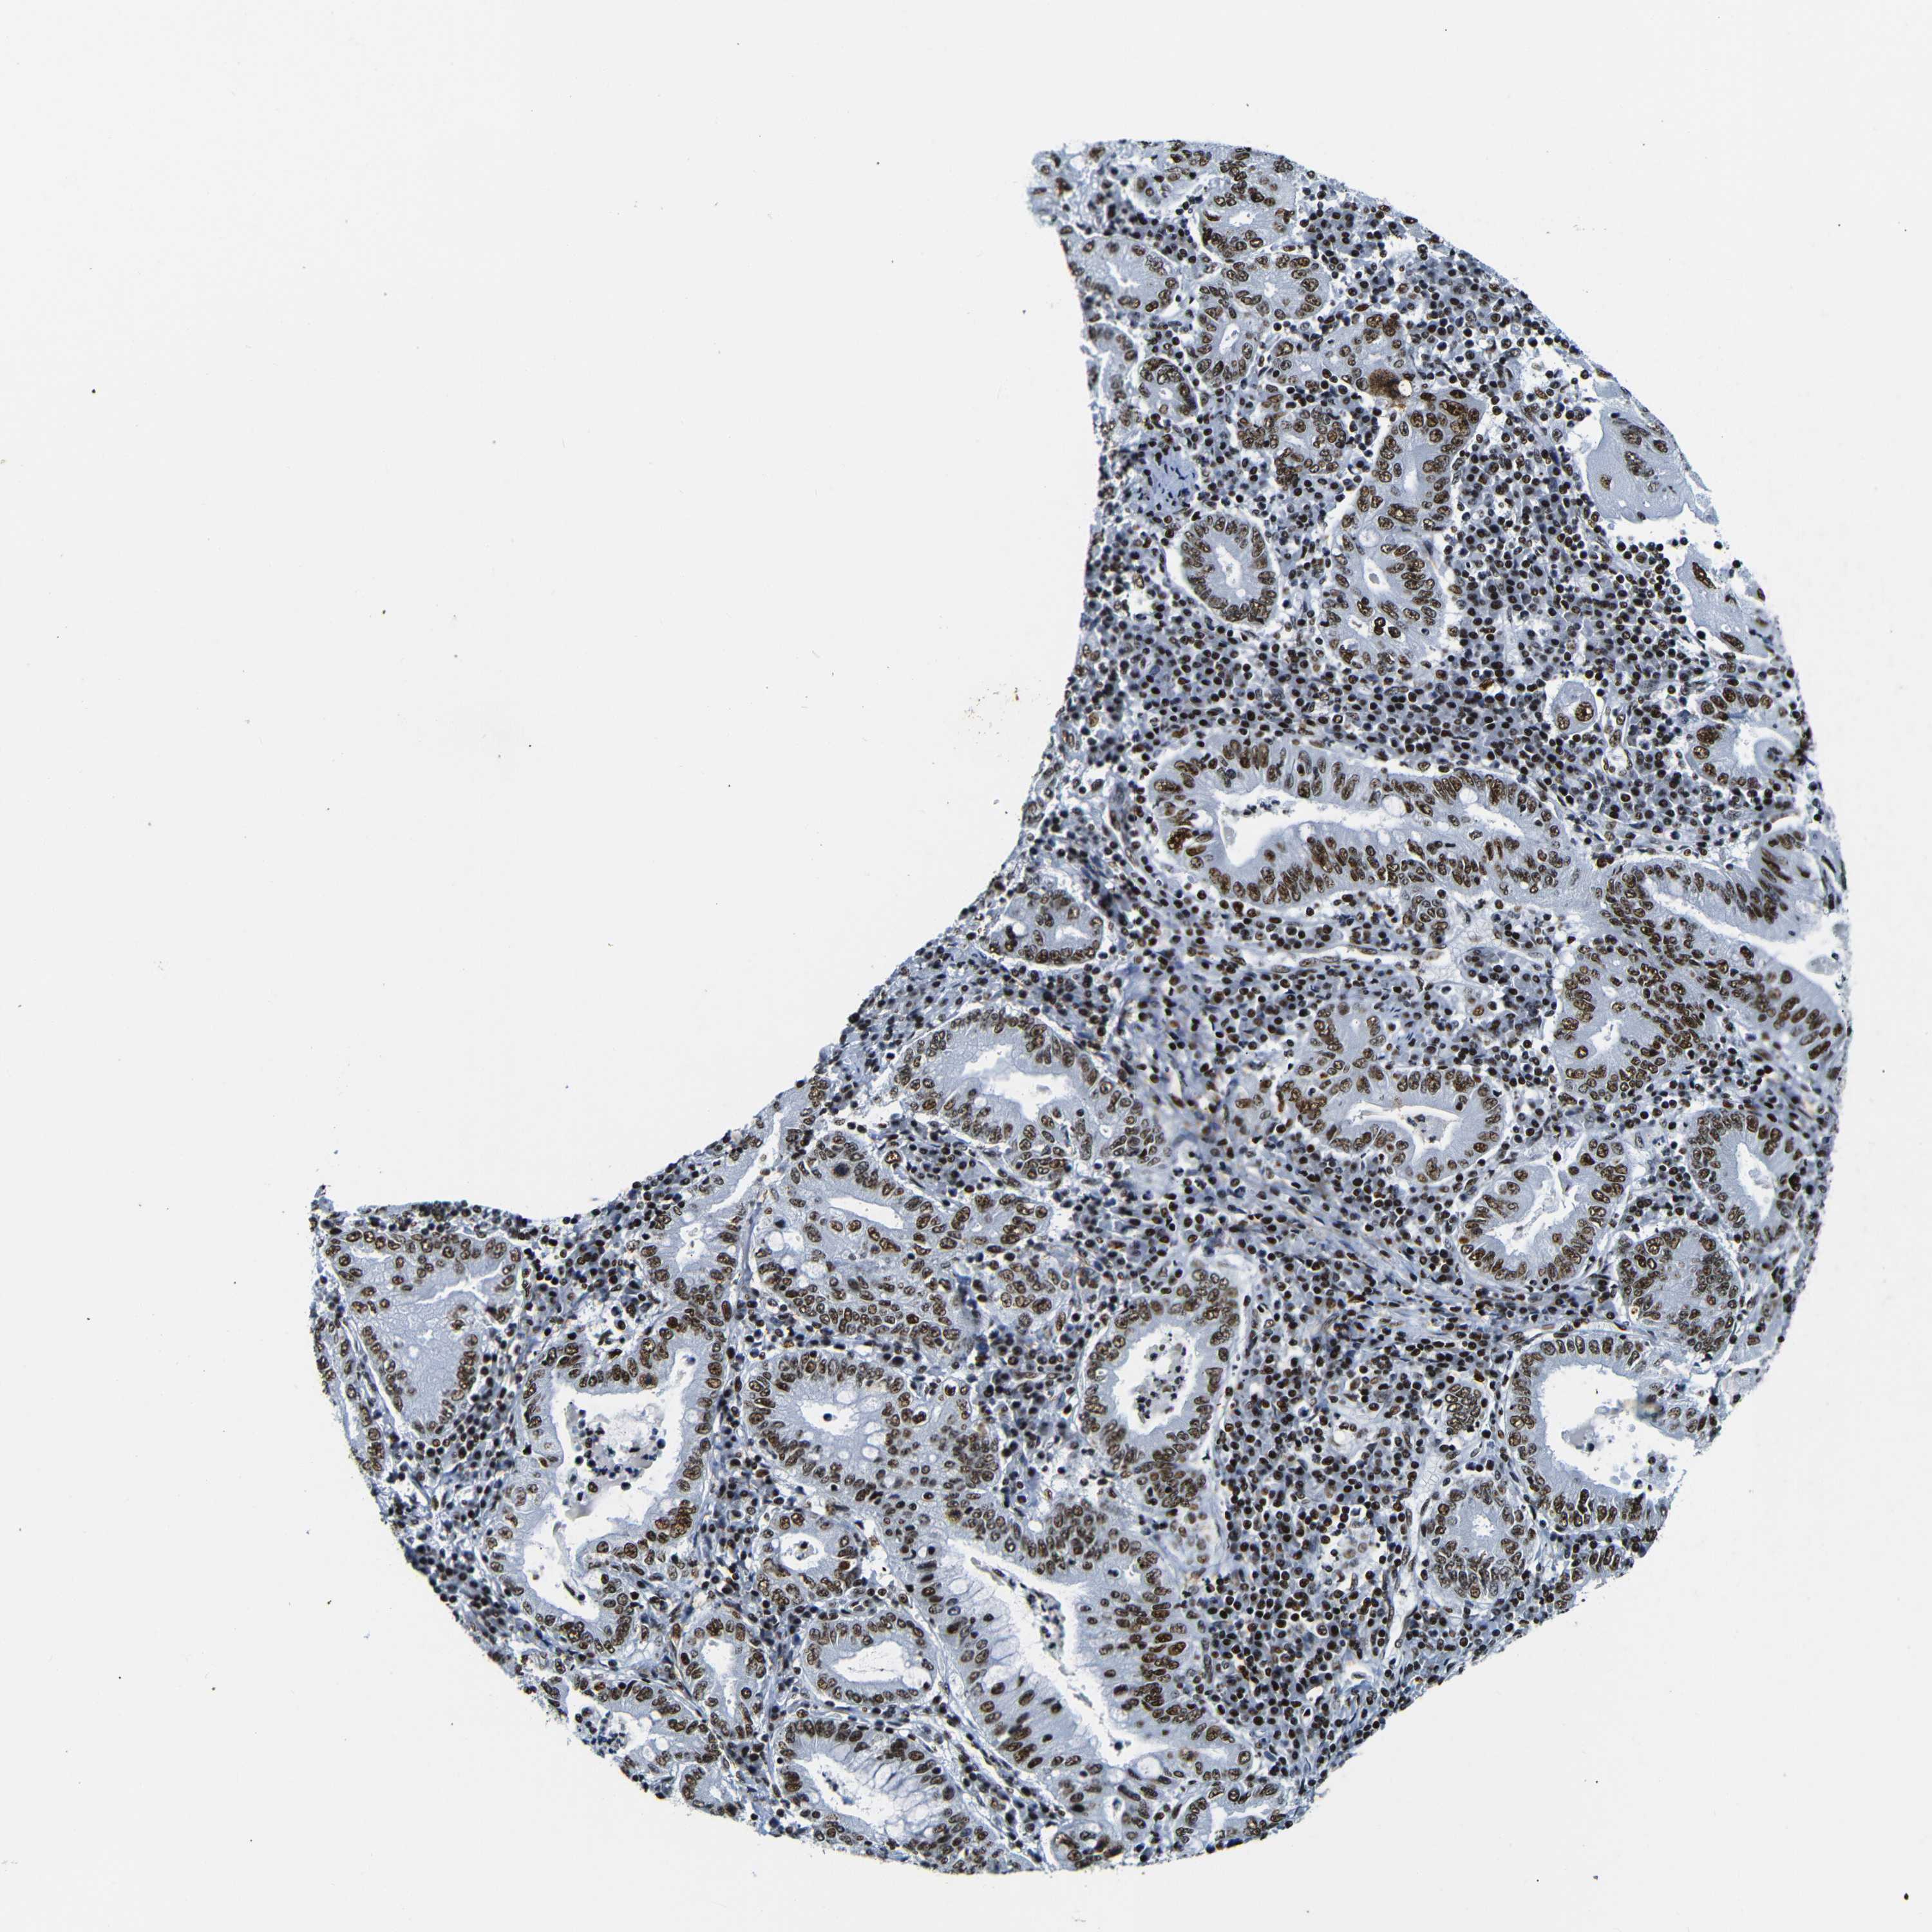

STOMACH CANCER - Protein expressioni

A mouse-over function shows sample information and annotation data. Click on an image to view it in a full screen mode. Samples can be filtered based on level of antibody staining by selecting one or several of the following categories: high, medium, low and not detected. The assay and annotation is described here.

Antibody stainingi

Antibody staining in the annotated cell types in the current human tissue is reported as not detected, low, medium, or high, based on conventional immunohistochemistry profiling in selected tissues. This score is based on the combination of the staining intensity and fraction of stained cells.

Each image is clickable and will lead to virtual microscopy that enables deeper exploration of all samples and also displays staining intensity scores, fraction scores and subcellular localization as well as patient and tissue information for each sample.

Antibody HPA061301

Antibody CAB013073

Staining

High

Medium

Low

Not detected

Intensity

Strong

Moderate

Weak

Negative

Quantity

>75%

75%-25%

<25%

None

Location

Nuclear

Cytoplasmic/membranous

Cytoplasmic/membranous,nuclear

Adenocarcinoma, NOS

Adenocarcinoma, High grade